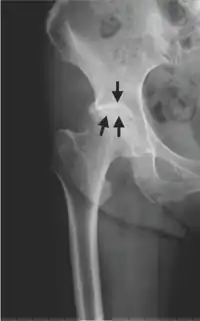

| Radiograph taken at onset of severe right hipjoint pain showing KL grading I hip OA | |